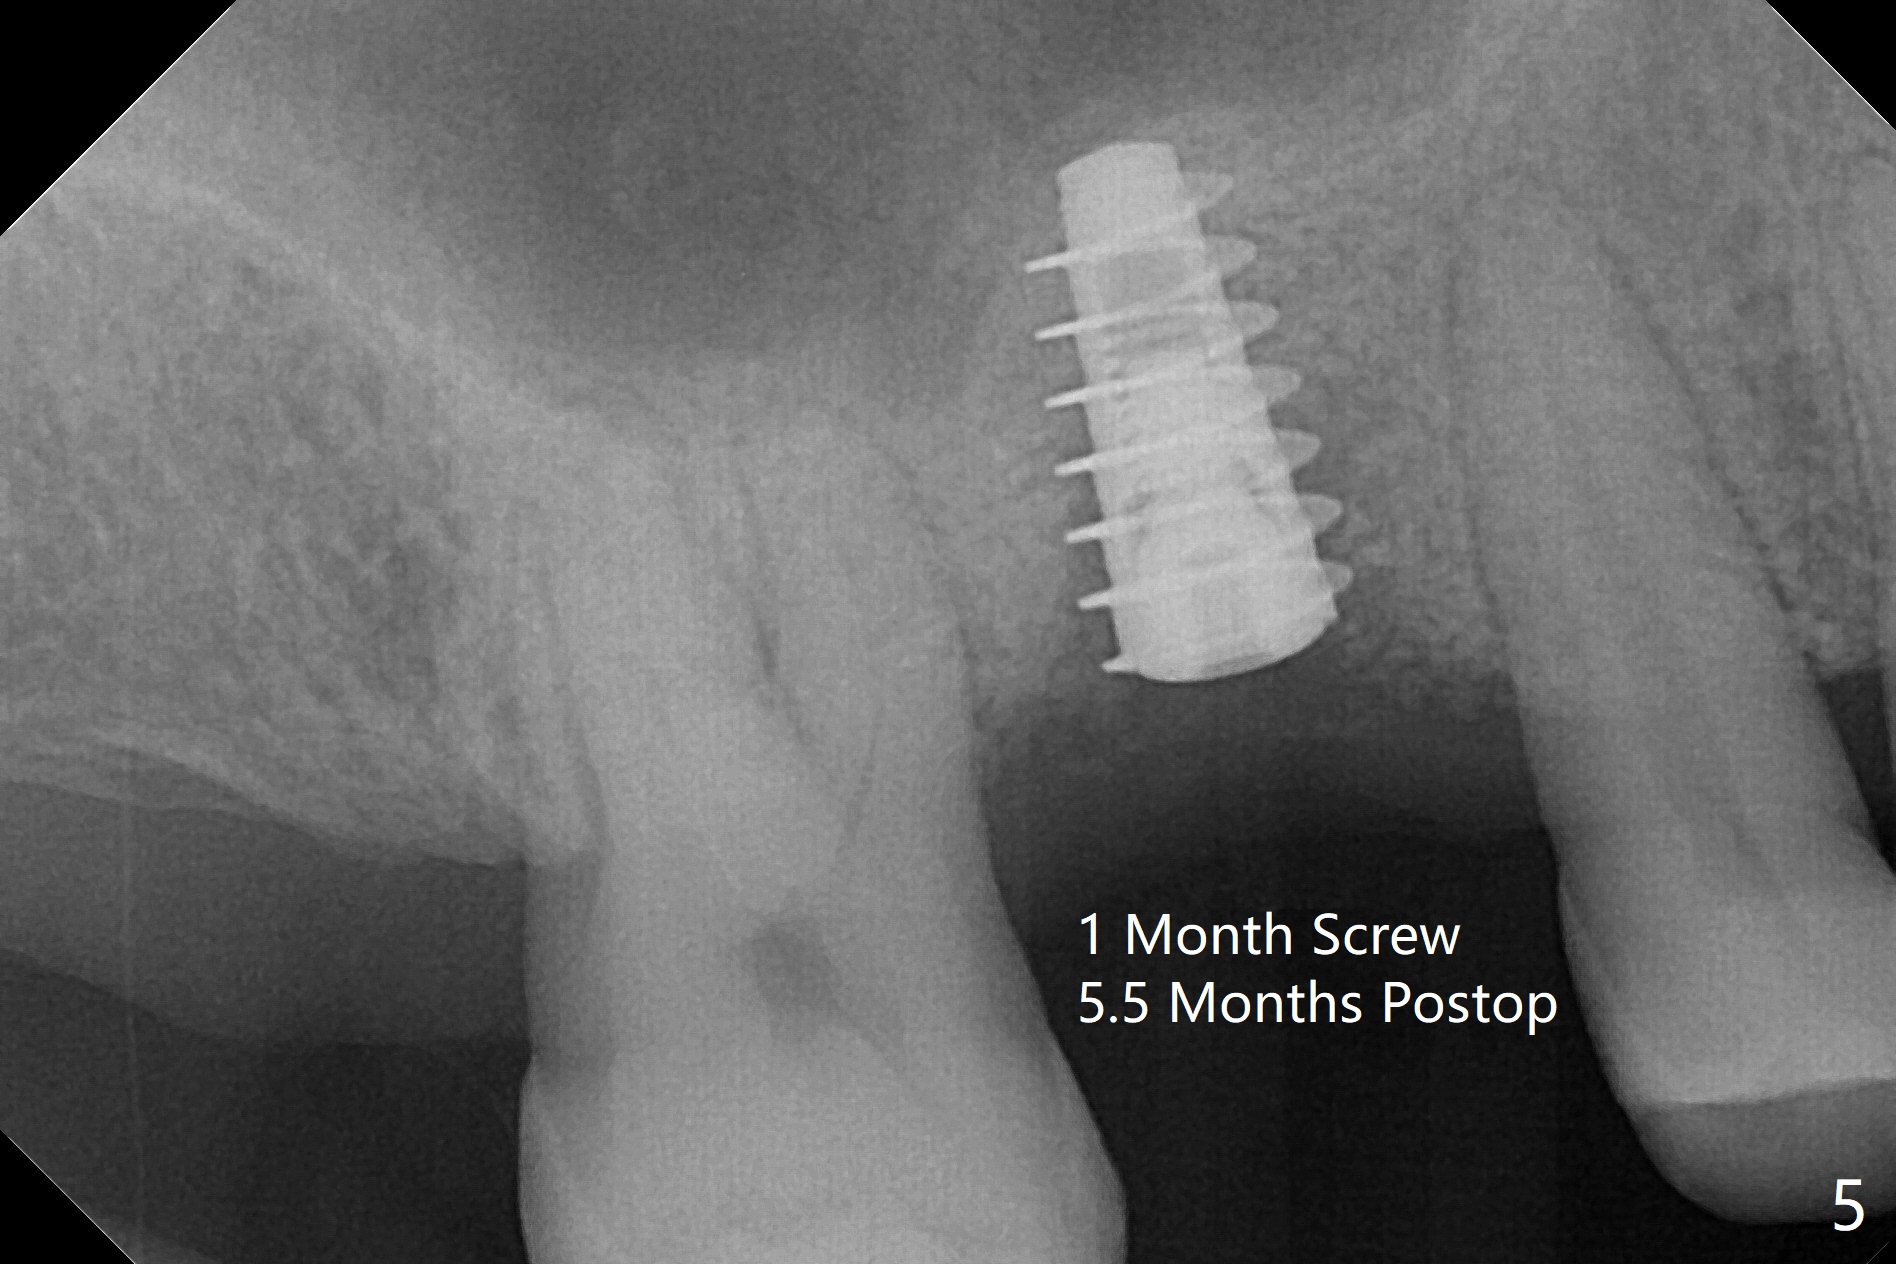

60岁男以前就害怕牙科治疗,一年前做一侧肾上腺切除,现在更紧张,不过挺配合。右上6手机切断拔除,虽然近中颊侧牙槽窝破坏厉害,中隔还很大(图一:S),利用导板顺利完成钻洞和提升术(图二:*)。植入正式植体后,放置第一轮粘性骨粉,至植体水平(确保植体深部周围没有缺失)而不影响基台置入,近中有不足之处(图三:*),第二轮骨粉补充(图四),最后覆盖PRF膜,临时牙冠固定。The crown/abutment/implant are found to have mild mobility 4.5 months postop, as related to #19 infection. A healing screw is placed. One month later, the wound heals; the bone density in the sinus increases (Fig.5 *), while that coronal to the implant decreases (^).愈合帽放置4个月,伤口还没有完全愈合,翻瓣后发现远中螺纹表面肉芽组织覆盖,去除后者,第一螺纹暴露。放置愈合基台后,从颊侧往远中缺陷填入骨粉(图六:*),缝合,覆盖树脂敷料。